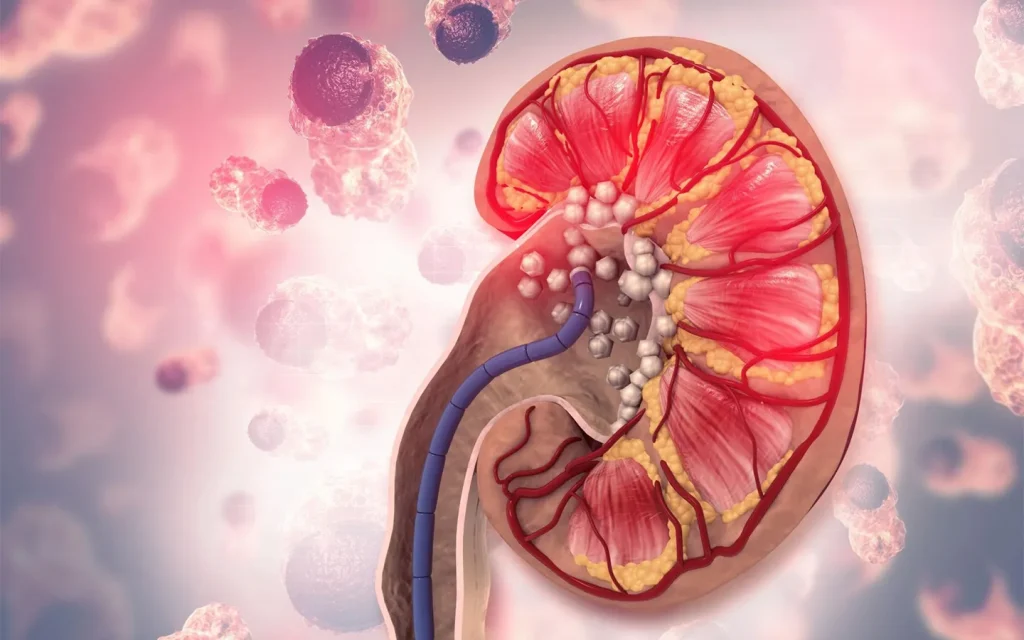

سنگهای کلیه، رسوبات بلوری شکل در مجاری ادراری یا لگنچه کلیه هستند. شایعترین نوع آنها، سنگهای کلسیم اگزالات هستند، اما سنگهای اسید اوریک یا سنگهای کلسیم فسفات نیز دیده میشوند. بسته به محل تشکیل، به آنها سنگهای کلیه، سنگهای حالب یا سنگهای مثانه گفته میشود. به طور کلی، همه آنها با عنوان سنگهای ادراری شناخته میشوند.

وقتی سنگها از حالب باریک عبور میکنند یا در آنجا گیر میافتند، فرد دچار درد شدید میشود که به آن کولیک کلیوی (درد شدید و متناوب کلیه) گفته میشود. سنگ کلیه میتواند با دارو درمان شود، به روش جراحی برداشته شود یا با استفاده از امواج صوتی خرد شود.

علائم شامل درد شدید و ناگهانی در ناحیه کلیه است که بسته به محل سنگ ممکن است به قسمتهای دیگر بدن منتشر شود. تکرر ادرار، مشکل در ادرار کردن یا خون در ادرار میتواند از دیگر نشانههای سنگ کلیه باشد. این مشکلات همیشه باید توسط پزشک بررسی شوند. در موارد نادر، ممکن است پشت این علائم تومور وجود داشته باشد. همچنین، سنگهای کلیه میتوانند باعث افزایش احتمال بروز عفونت لگنچه کلیه شوند.

اغلب سنگهای کلیه آنقدر کوچک هستند که بدون درد و از طریق ادرار دفع میشوند. سنگهای بزرگتر معمولاً زمانی مشکل ساز میشوند که از حالب باریک عبور کنند یا در آنجا گیر کنند. در این حالت کولیک کلیوی اتفاق میافتد که با درد شدید و گرفتگی در ناحیه کلیه همراه است. اغلب این دردها با حالت تهوع، استفراغ و تب نیز همراه هستند. واکنش بدن به درد شدید میتواند باعث اختلال در عملکرد روده و نفخ شکم شود.